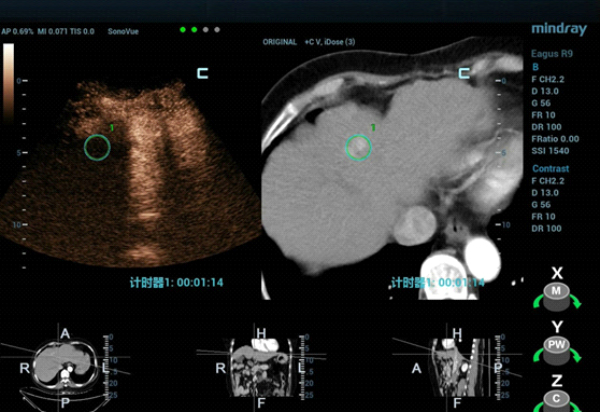

CT??? ??? S4?? ??? ??? ?? ???????? ??? ?????. CEUS(Contrast-Enhanced Ultra Sound)????? ?????? ??? ??? ??? ??? ???? ? ??? ???? ???? ??? ???????.

??? ??? ?? ????? ???(MWA)? ?? ?????? ?? ?????? ??? ???? ??? ?? Contrast-enhanced CT? ???? ??? ?? ??? ??? ?? ??? ?? ??? ????? ???? ???? ????? ??(MWA)? ??? ???????.

??? ????? ??? 2D ??? ??? ???? ???? ???? ??? ? ????? ??? ??? ?? ?????? ???? ?? ??? ???? ???? ??? ? ?????. ??? ??? ???? ??? ?? CT ??? ??? ???? ??? ??? ??? ?? MWA? ?? ???? ??? ???? ?????. CEUS(Contrast-Enhanced Ultra Sound)? ???? ?? ? ??? ??? ????, ?? ? ?? ??? ???? ?? ?? ??? ???????.?

?? ??? ??? CEUS(Contrast-Enhanced Ultra Sound)? ???? ????? ??? ??? ??? ???? ??? ? ??, ????? ???? ???? ????, ?? ??? ?????? ??? ? ????. ??? ??? ??? ???? ??? ?? ????? ??(Ultrasound-guided MWA)? ???? ?? ??? ?????.